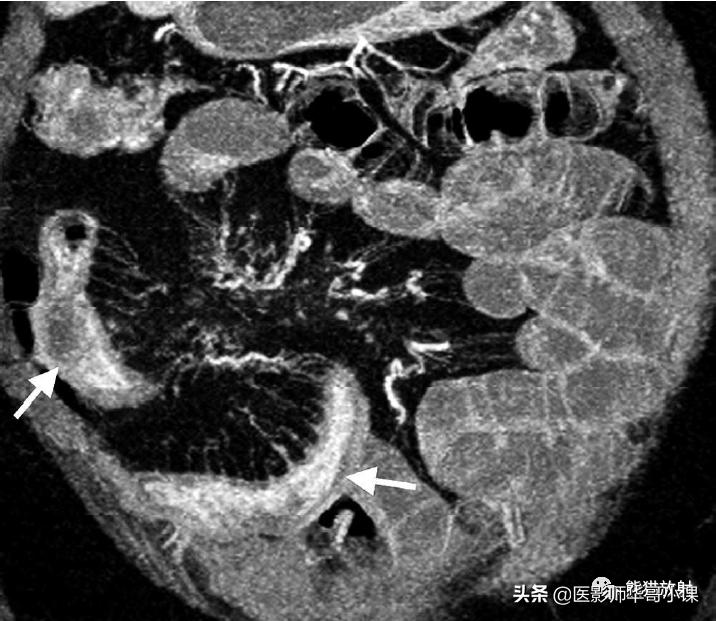

肠系膜异常在克罗恩病中很常见。肥厚的肠系膜脂肪组织,称为 肠系膜纤维脂肪增生 ,是克罗恩病的特征性表现。在横断面图像上可见肠系膜脂肪增多,对邻近肠襻产生占位效应,主要位于肠管的系膜侧(图)。临床上疾病处于静止期时仍然存在纤维脂肪增生, 直小血管充血(“梳子征”)则提示炎症处于活动期 。

活动性克罗恩病。小肠造影增强CT的MIP重建显示广泛的回肠克罗恩病(箭)伴肠系膜纤维脂肪增生和节段性充血。